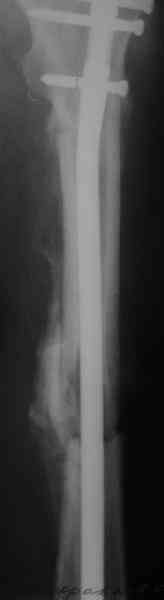

Судя по уровню перелома, винты в шейку избыточны, подойдет и диафизарный гвоздь. Все, что нужно, это тиски и труба. Загнуть сразу ниже отверстий градусов на 8-10, и вся недолга. Последние годы у нас это рутинная практика. Предызогнутые еще с завода гвозди неудобны тем, что они уже правый-левый.

Согласен, что 3,5 см укорочение этим снимкам не соответствует, за счет перелома и деформации - 1,5 см от силы. То есть либо ошибка измерения, либо приводящая контрактура, либо укорочение за счет другого отдела.

Согласен, что закрытый реостеосинтез с рассверливанием и коррекцией оси - это то, что надо. Мы бы ввели в центральный отломок статических 2-3 винта, и один динамический винт в дистальном отломке.